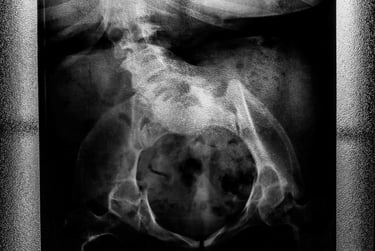

Carla, la protagonista, è una donna affetta da spina bifida, incontrata inizialmente come possibile soggetto per raccontare la disabilità. Quello che all’inizio appare come un progetto legato a una condizione fisica si trasforma presto in qualcosa di diverso: non più la storia di una disabilità, ma quella di una donna nella sua interezza.